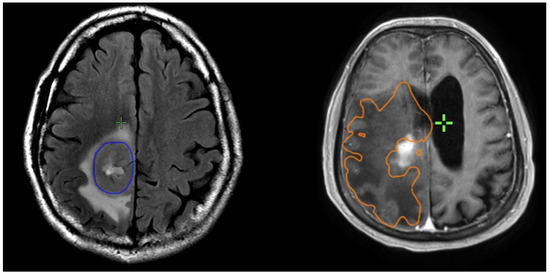

2.2. Radiological Volumetric Assessment

Preoperative and postoperative MRI scans were entered into the radiation planning programme and fused with the registration non-contrast enhanced CT scan. The T1, T2 and T1 gadolinium-enhanced sequences were utilised to manually create volumetric data on both pre- and postoperative scans. The volumes segmented and calculated are demonstrated in Figure 1. These include the preoperative gadolinium-enhancing abnormality (GTVT1gdpre), the preoperative T2 flair abnormality outside of the GTVT1gdpre (GTVT2pre), the postoperative gadolinium-enhancing abnormality subtracted by the blood products on T1 sequence (GTVT1gdpost), and postoperative T2 flair abnormality subtracted by the surgical cavity (T2post). A T2/T1 ratio was calculated from the preoperative volumes (GTVT2pre/GTVT1gdpre), with examples of high and low ratios demonstrated in Figure 2. This T2/T1 ratio was recorded as a continuous variable as well as divided into quartile groups 1–4.

Figure 1. Measurement of T1gd volume (GTVT1gdpre: blue) and T2 volume (GTVT2pre: orange) on respective MRI T1g sequences on right and T2 flair sequence on left.